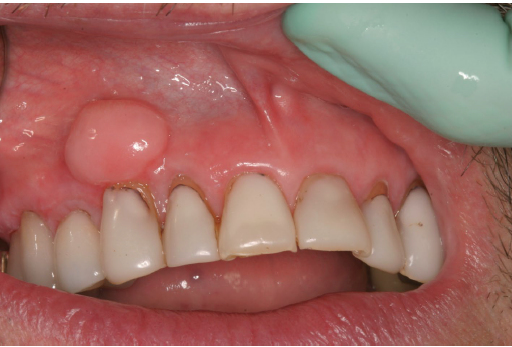

post surgical hyperostosis

tumor like (reactive) growth of bone at the surgical site

in periosteum following periodontal surgery such as a gingival graft

female patients, anterior mandible